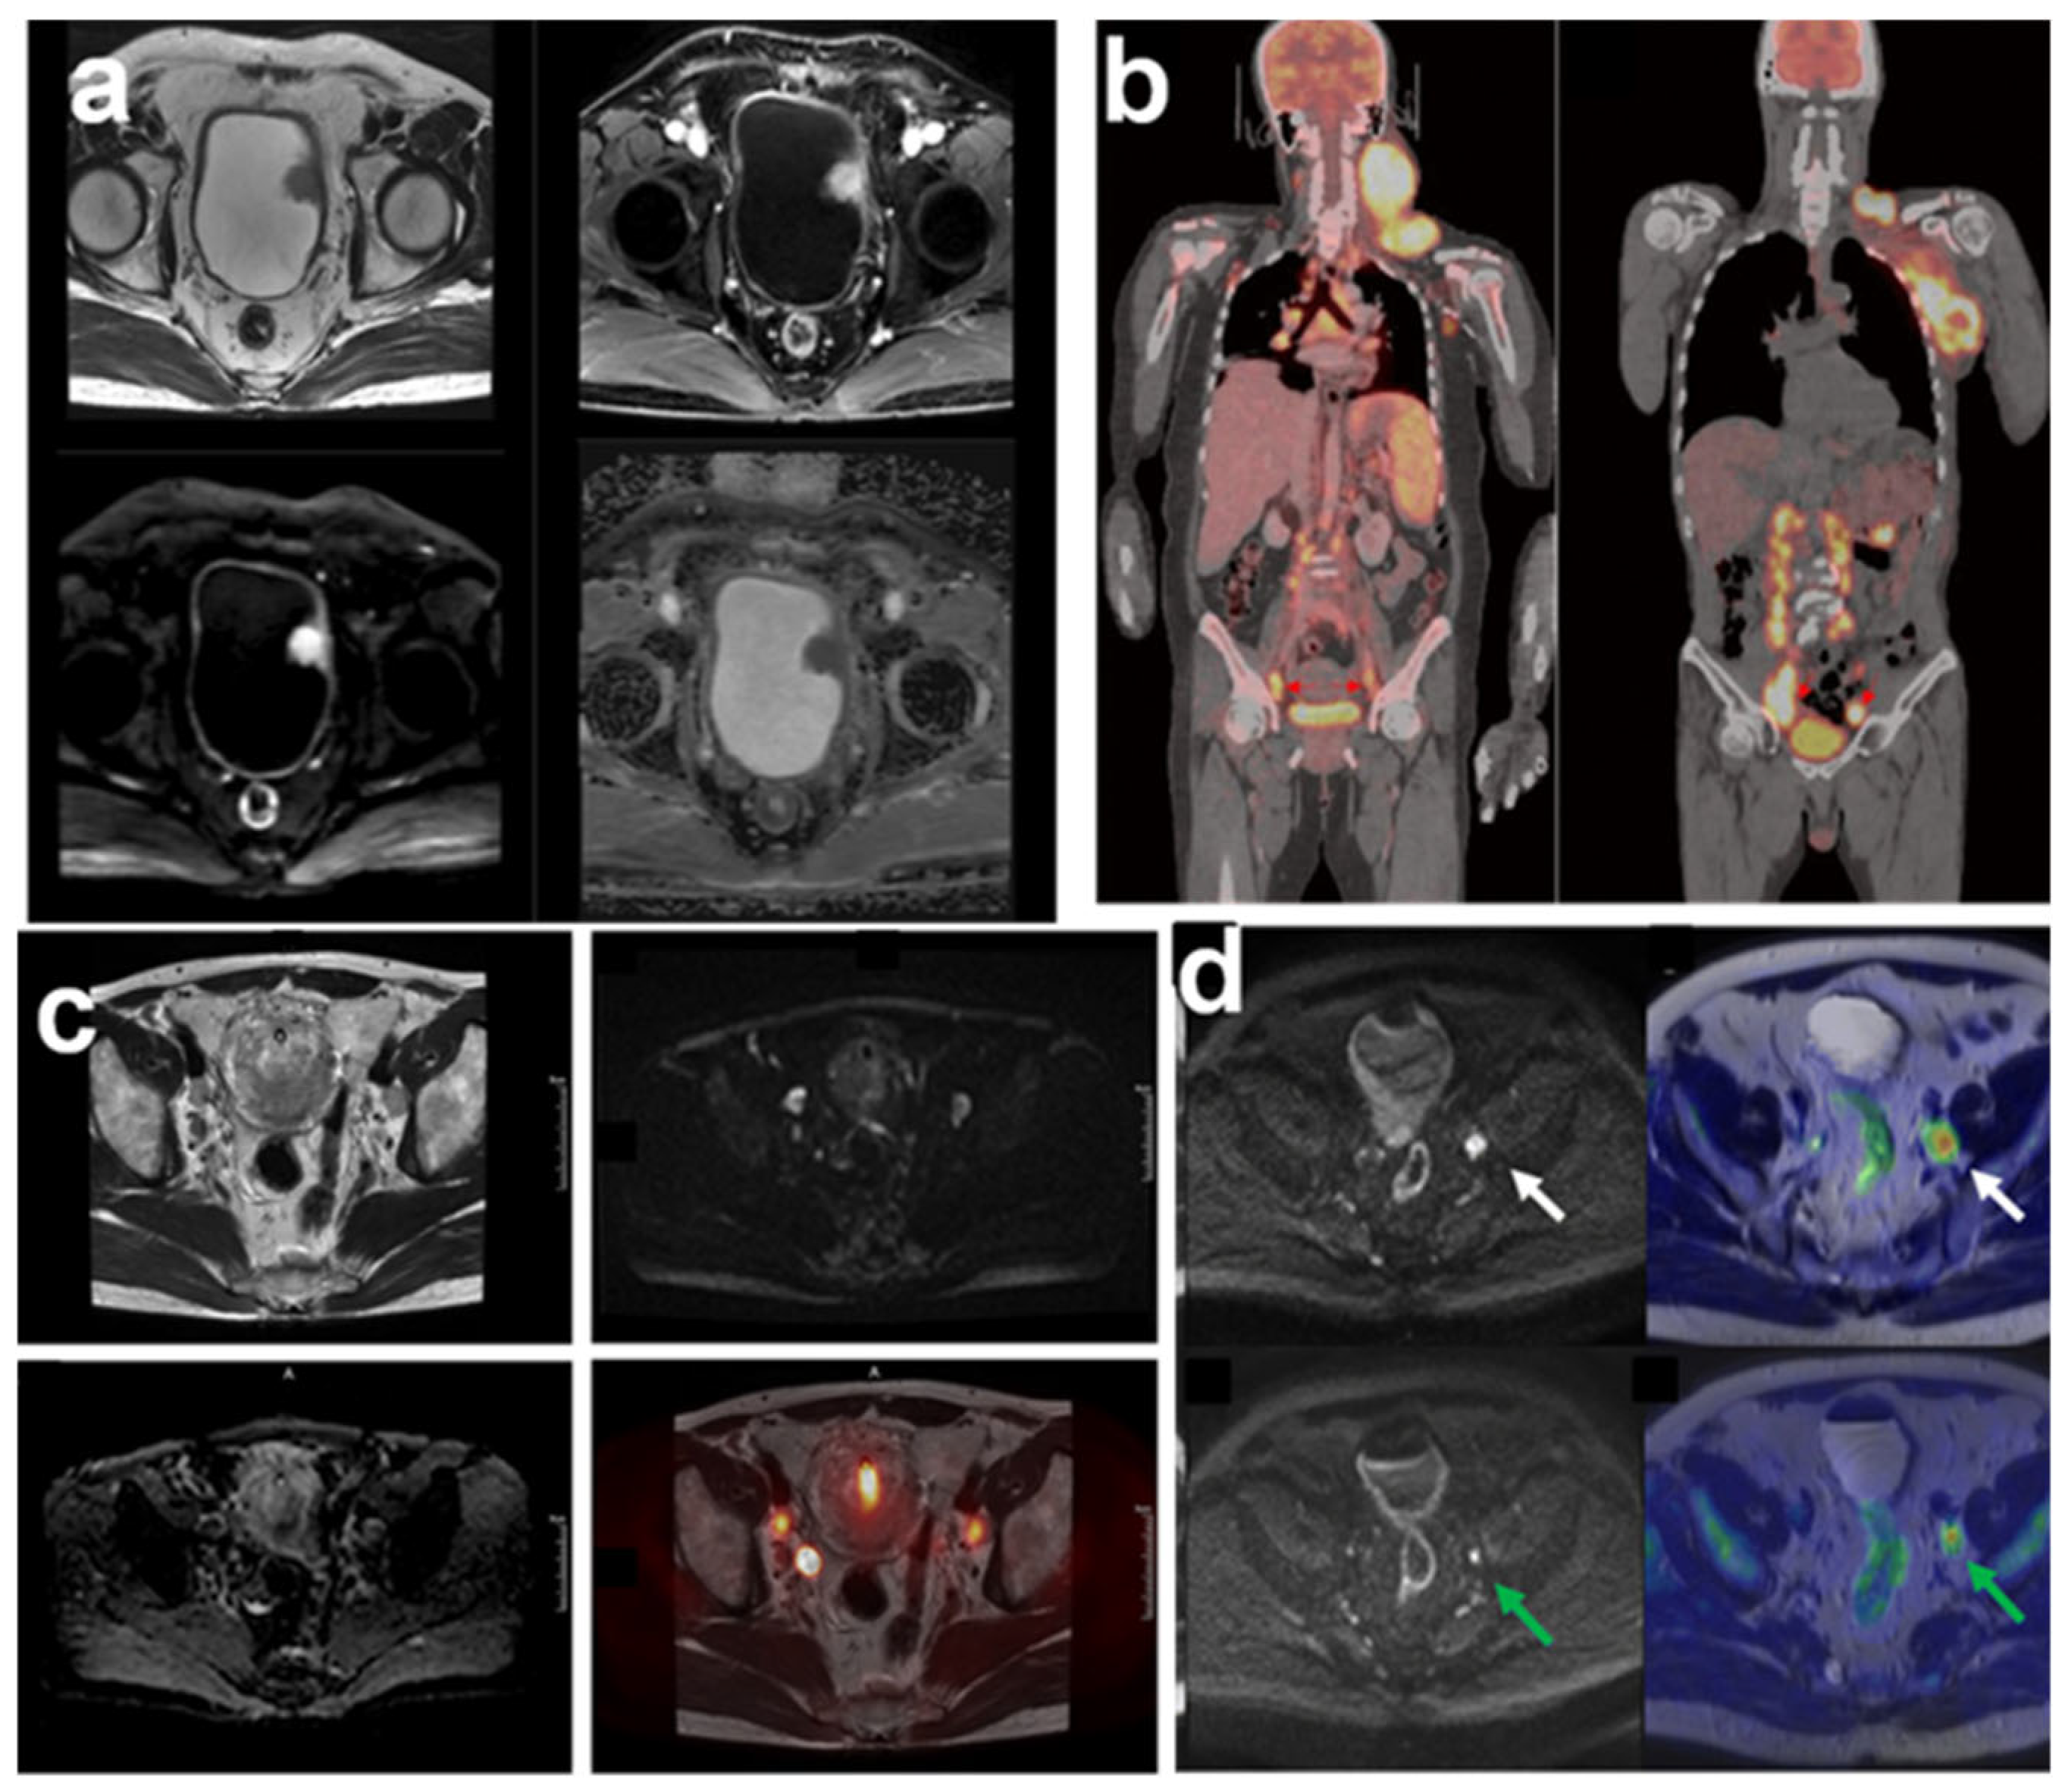

3. Targeted Molecular Imaging of Bladder Cancer

4. Integration of Mass Spectrometry and Molecular Imaging for Bladder Cancer Biomarker Detection as Advancing Precision Oncology